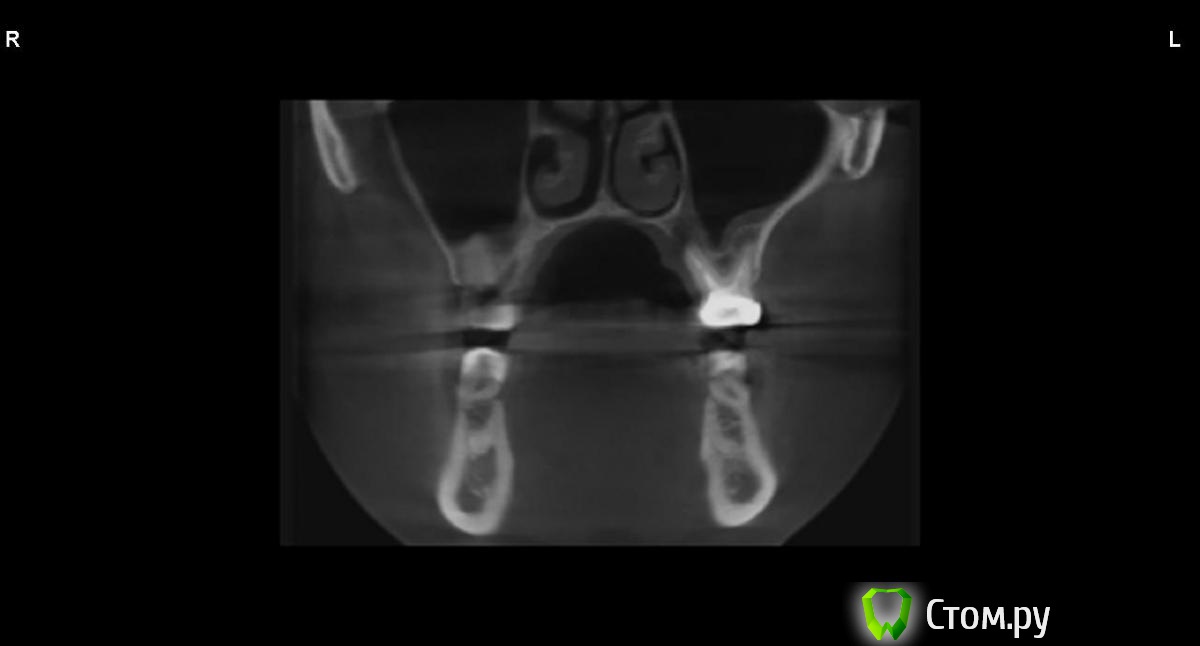

jm3300 Опубликовано 9 сентября, 2014 Автор Поделиться Опубликовано 9 сентября, 2014 вот, набросал Ссылка на комментарий

АнтонТЛТ Опубликовано 9 сентября, 2014 Поделиться Опубликовано 9 сентября, 2014 (изменено) это нижняя носовая раковина, возможно Изменено 9 сентября, 2014 пользователем АнтонТЛТ Ссылка на комментарий

АнтонТЛТ Опубликовано 9 сентября, 2014 Поделиться Опубликовано 9 сентября, 2014 я понял что это)))это артефакт от зуба, обратите внимание на правую сторону, там в пазухе тоже зуб есть, после эндодонтии)) Ссылка на комментарий